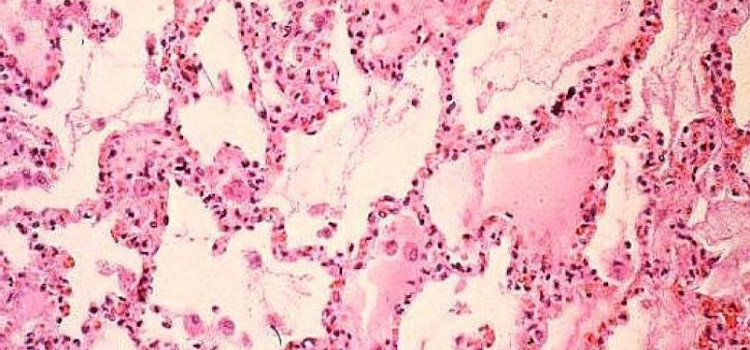

Desvelan el papel clave de una nueva proteína en el cáncer de pulmón

27.01.2020

Una proteína, cuya función se desconocía hasta ahora, ha resultado fundamental en el desarrollo del cáncer de pulmón